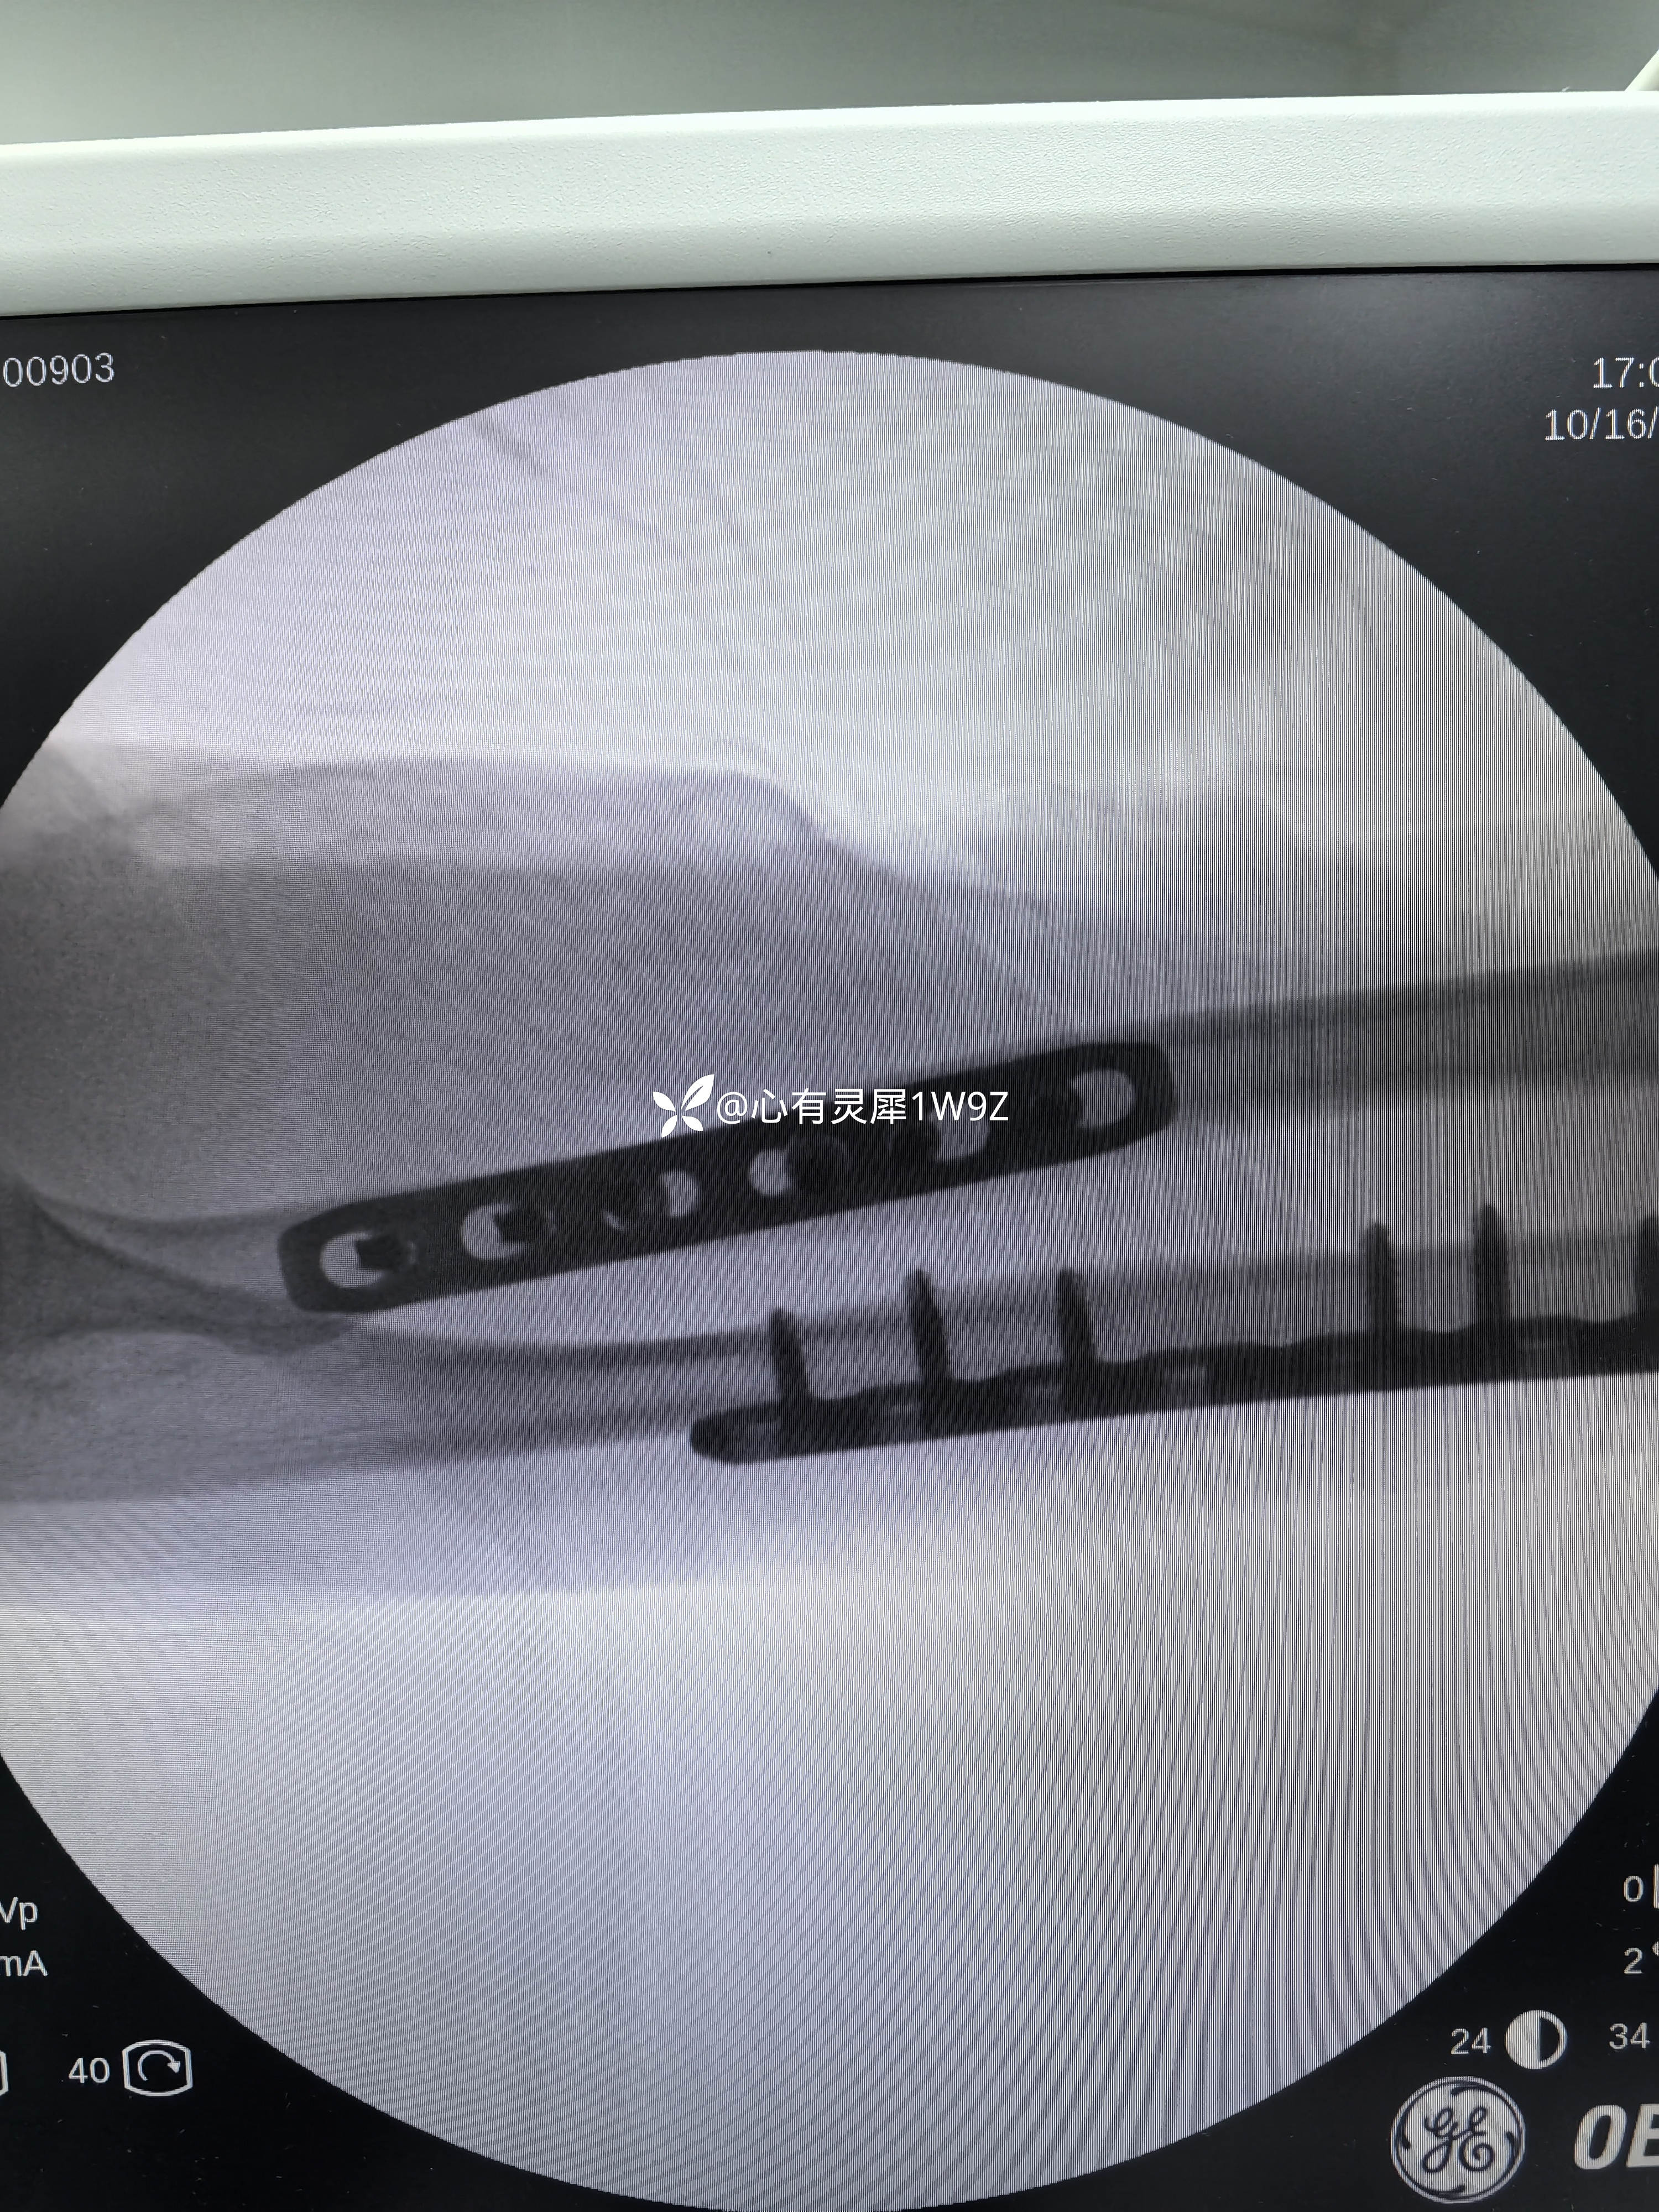

【治疗经过及结果】:臂丛麻醉下切开复位内固定手术。

桡骨近端骨折,手术切口选择一般有背侧入路掌侧入路两种选择。背侧入路需要显露保护桡神经深支,掌侧入路需要保护桡动静脉,结扎桡动脉分支,近端也要小心桡神经深支。各有各的特点,根据自己的经验选择切口。手术中要有耐心,小心显露,不能急躁。